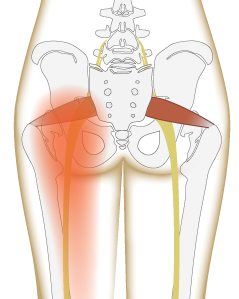

·原因: 疼痛大约在屁股摺痕处。尤其是在你膝盖伸直且将身体向前弯腰时,症状会更明显。这种型态的疼痛表示是连接到骨盆的腘绳肌肌腱受伤,这通常是因为过度的拉扯腘绳肌。(如在瑜伽中:当瑜伽练习者需要保持双腿笔直向前弯曲,然后强迫自己摆姿势时,可能最终会损伤肌腱。)当我们的肌腱受伤,腘绳肌会自然的收缩,试图去保护受伤的肌腱。然而我们认为的是:"腘绳肌紧绷又疼痛,要去伸展它,疼痛自然会消失了",而这样的方式却无法让肌腱修复,反而是重复使其受伤——过度伸展然后再受伤,这样的循环会使复原时间变更长。较好的方式是借由适当地收缩腘绳肌来增加受伤区域的循环,如果可以的话,做简单轻微的伸展。当疼痛急性期结束后,你可以慢慢增加伸展的角度。您的朋友或患者中,是否有人向你这样抱怨过:我的髋部在走路、睡觉时会痛,物理治疗师建议他作核心运动,骨科医师诊断他是梨状肌症候群,也试过请按摩师放松他紧绷的髂胫束。经过仔细的检查后,确认了他疼痛的位置,疼痛的症状都指向无力的外展肌群,造成骨盆位置不良,导致某些肌肉群去代偿。当开始训练他的外展肌群,很快地他的疼痛就不见了。此型态的疼痛通常会出现在臀部外侧或上侧,可能会向下至大腿的外侧。它通常是在散步跟晚上侧躺在患侧时更糟。薄弱的外展肌群,紧绷的髂胫束可能是引起疼痛的一种因素。这种疼痛常被认为是髂胫束的问题,所以借由伸展髂胫束,或用滚筒去放松,这会非常有效,但并没有解决问题的根源-外展肌无力,除非你去加强肌力,否则问题会一再出现。你需要锻炼你的髋外展肌,可以利用单脚站,另一侧大腿对抗重力做髋外展动作,两侧轮流施行,让髋外展肌做为稳定以及动作的功能角色。大家知道坐骨神经分布的范围到底有多大吗?它是你的身体里最长的一条神经,从下段脊椎一路延伸到脚,而且它也非常的粗,大概就像是你的小指头一样粗,穿过你的脊椎与髋关节。因为这条神经粗又长,它可能在很多地方被挤压到,而造成类似坐骨神经痛的症状。两个常见被挤压位置在下背部(腰椎椎体间)跟紧绷的梨状肌下面。梨状肌是一条很小的肌肉,当它太紧绷时可能会造成很多困扰。它位于髋部深处,在髋关节弯曲状态下,负责带动髋关节外转跟外展。紧绷的梨状肌会造成屁股痛,但当它压迫到通过梨状肌下面的坐骨神经时,就会使情况变得更糟。疼痛通常会出现在臀部中间的位置、下背部,或任何坐骨神经通过的地方。症状也有可能是脚麻或无力。如果是因为椎间盘突出引起的坐骨神经痛,是比较大的问题,超过我们本篇所要介绍的范围,在物理治疗师的指导下,加强核心肌群的运动是个不错的方式。如果疼痛是因为紧绷的梨状肌,我们可以着手于放松紧绷的肌肉。·较好的方式:利用我们常见的”收缩-放松-伸展原则”(Contract-Relax-Stretch principle)步骤①:从收缩周围肌肉开始(尤其是臀大肌),来增加此区域的血液循环。步骤②:然后我们可以轻轻的收缩梨状肌 (contract the piriformis ),让它慢慢放松掉原本慢性的收缩(如果不会感到疼痛),搭配温和的伸展。我们可以借鉴瑜伽中的动作,像是勇者式二(Virabhadrasana 2)、侧三角伸展式(Utthita Parsvakonasana)跟蚌蛤式都可以让梨状肌收缩,而在站姿下利用椅子做扭转动作,以及半鱼王式(Ardha Matsyendrasana)是伸展梨状肌最好的选择,因为此姿势会让你的脚处于弯曲、内收,但不会外转的姿势,这对于梨状肌是比较温和的姿势。步骤③:当你觉得你已经准备好在伸展加入外转的动作时,你可以选择穿针引线式(Thread-the-needle pose)来取代鸽式(Pigeon)或牛面式(Gomukasana),这会让使梨状肌受到较小的力矩。当你练习这些动作后,你就可以试着做鸽式(Pigeon)或牛面式(Gomukasana)。PS:但有些学生即使练习很久也还是没办法完成鸽式或牛面式。此外,由于过紧的内收肌群会使髋关节呈现内转姿势,使梨状肌产生额外的压力进而压迫到神经,所以也可使用相同的方式来舒缓内收肌群的慢性紧缩。紧绷的腘绳肌也会造成坐骨神经受压迫,所以对于缓解此肌群的张力也是很有效果的。请记住,即使最简易的腘绳肌伸展运动也可能造成一位有坐骨神经痛症状的人极大地疼痛,所以建议用前面提及到第一种臀部疼痛的腘绳肌伸展原则。 请记住,一个疼痛症状,有可能是许多原因造成的。如果您的疼痛在你经过一番努力后,仍然存在,应该是要去寻求专业建议的时候了。